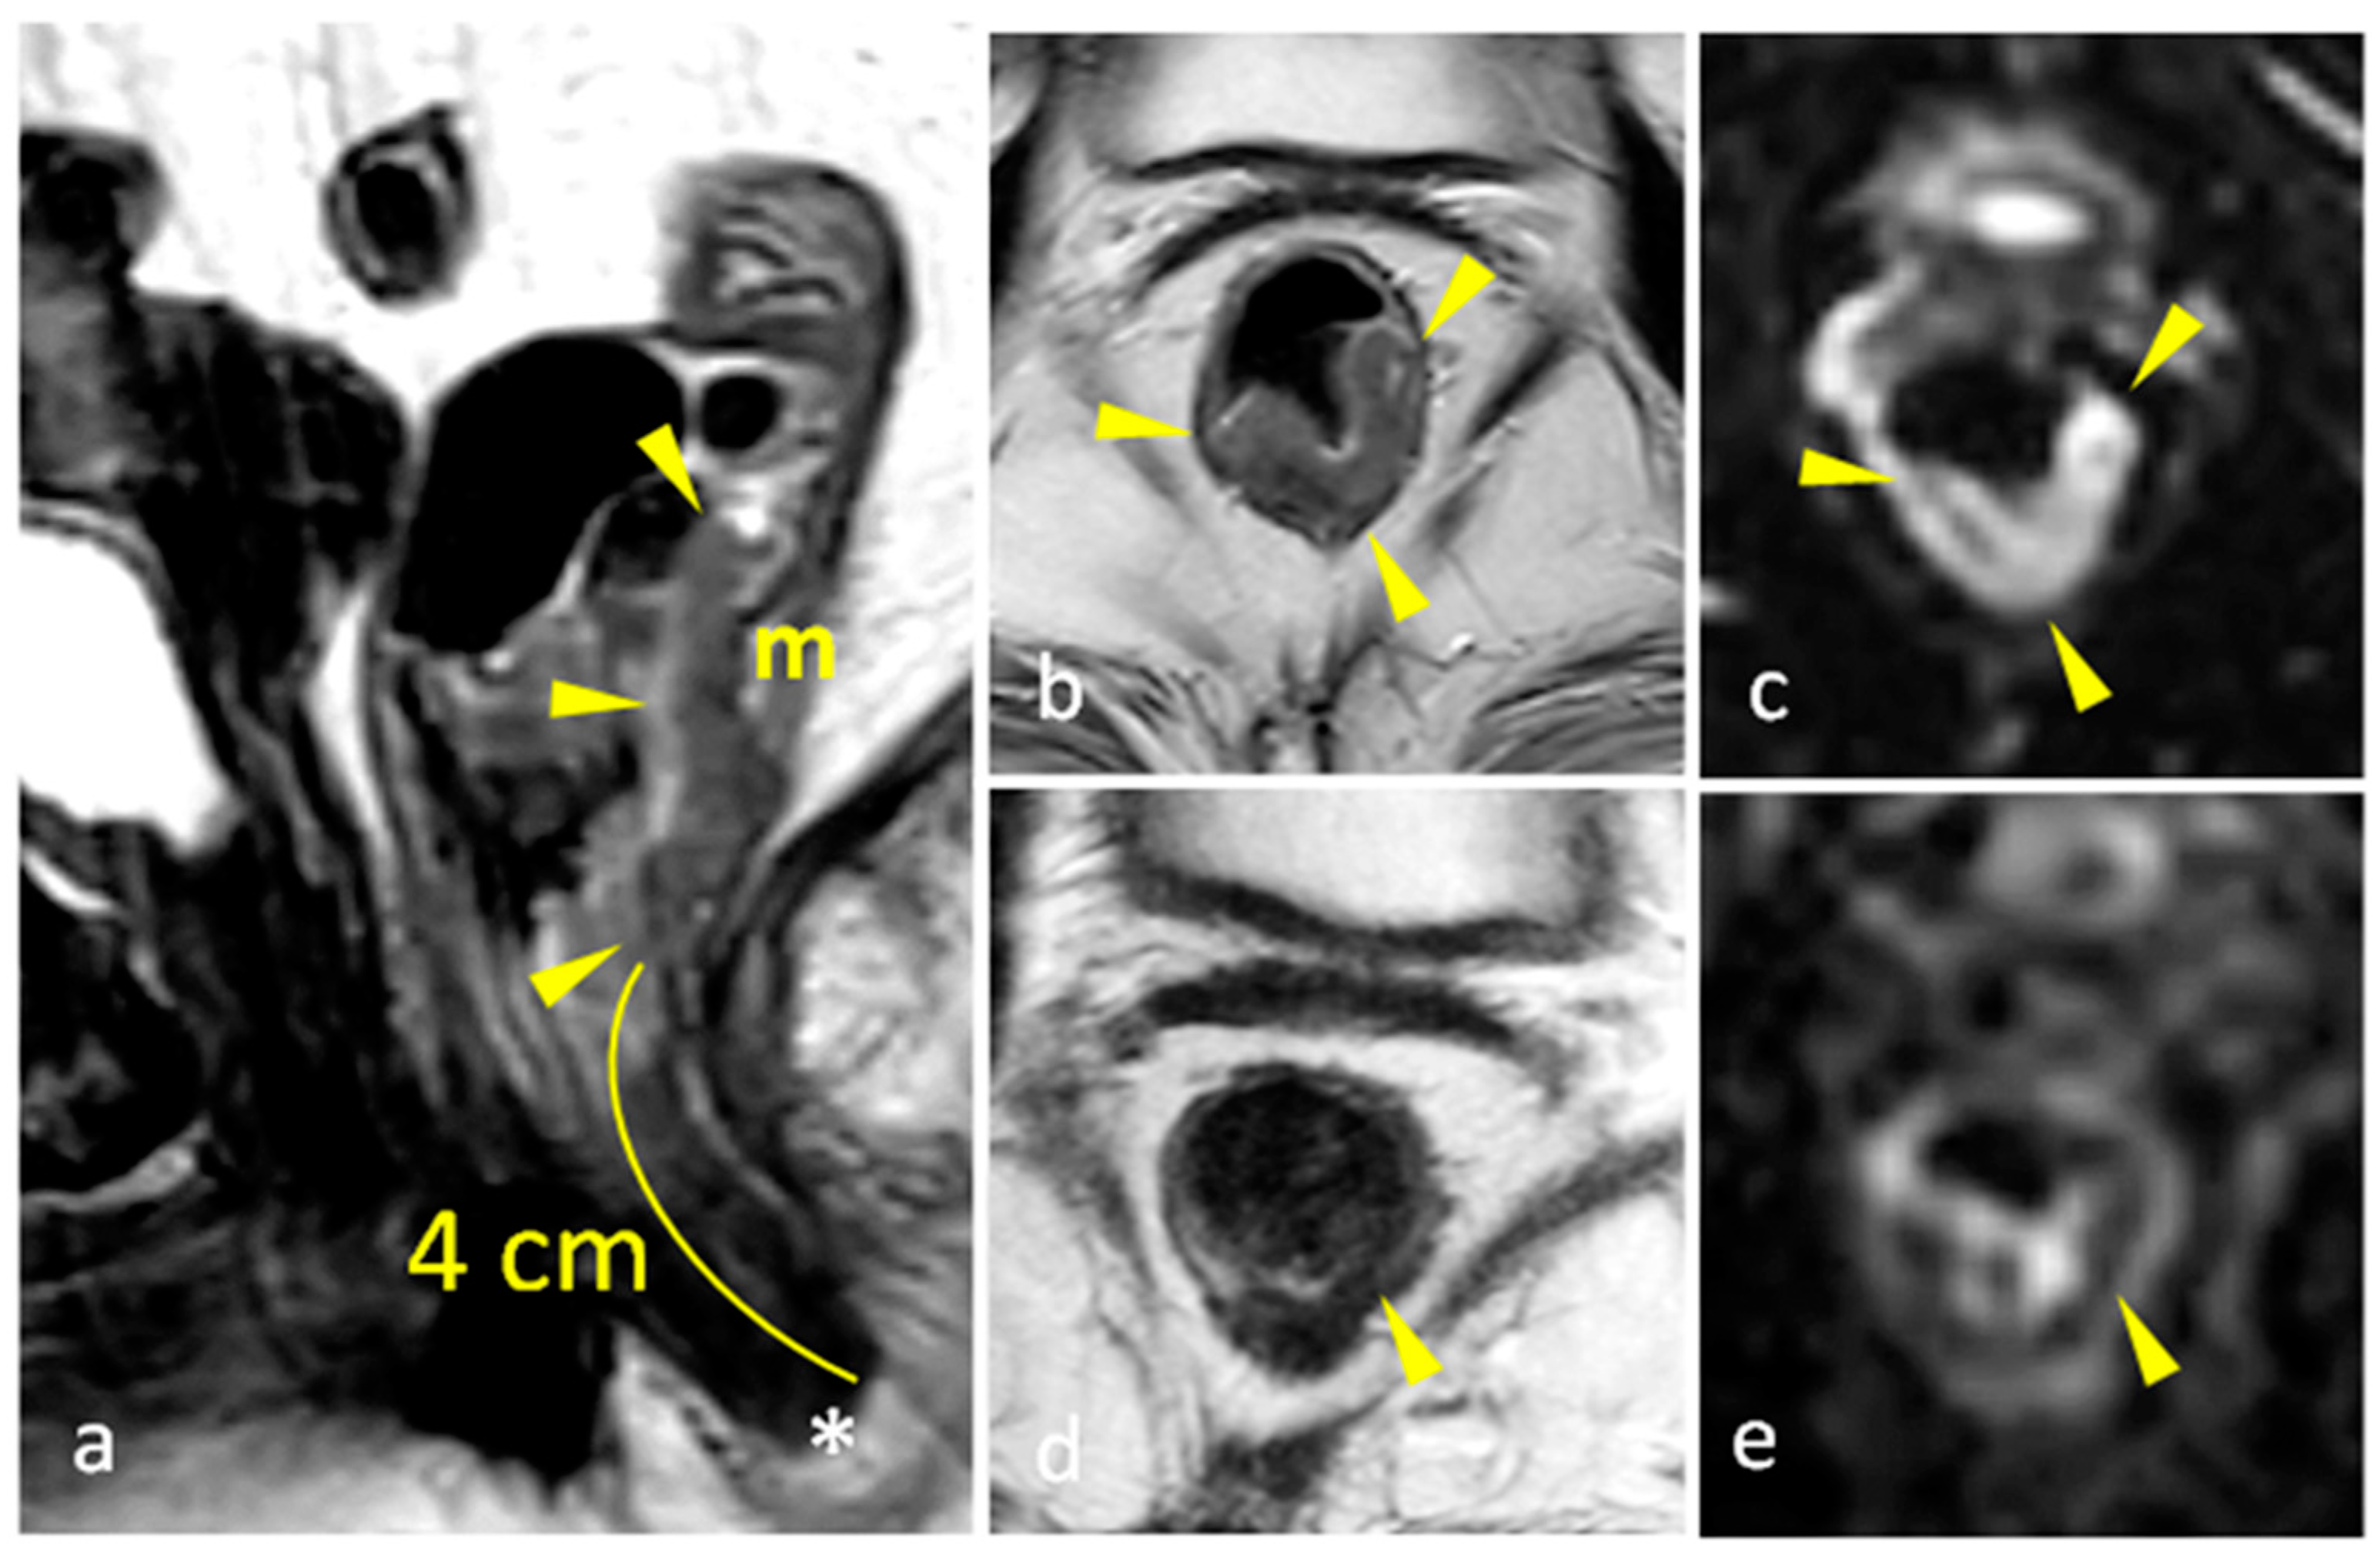

| mrTRG | 1 | Complete Radiologic Response (i.e., no evidence of tumor) |

| 2 | Good Response (i.e., dense >75% fibrosis with no obvious residual tumor) | |

| 3 | Moderate Response (i.e., >50% fibrosis or mucin with a minority of visible tumor) | |

| 4 | Slight Regression (i.e., <50% fibrosis or mucin with a majority of visible tumor) | |

| 5 | No post-treatment changes | |